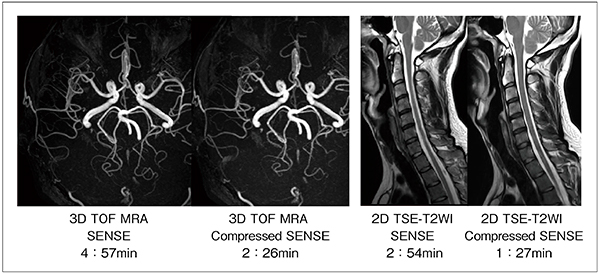

Compressed SENSEは,前述した技術により臨床応用へ高い期待が持てる。3D撮像のみならず,ルーチン検査のほとんどを占める2D撮像にも対応しているため,EPIやradial scanを除く,現状の撮像プロトコールにほぼ制限なく対応が可能である。また,50%以上の短縮率を図っても,画像劣化を最小限に抑えた画像が得られる(図3)。さらに,Optimized Variable-density Samplingは,効率的な撮像時間短縮を図る要素であるとともに,k-space中心部を密にランダムサンプリングすることから,モーションアーチファクトを減少させる特長も生まれる。図4は,2D-高速スピンエコーを用いたT2強調画像である。脊髄内に発生したモーション性のゴーストアーチファクトが,Compressed SENSEを併用した場合,減少していることが確認できる。

図4 SENSEとCompressed SENSEの比較画像